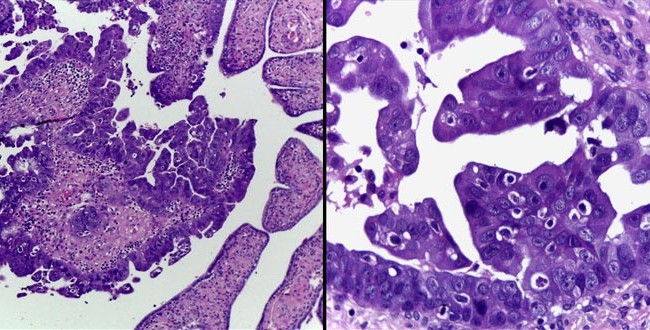

Carcinoma seroso intraepitelial tubario

Autores: Paradeda, Maria Eugenia y Garcia Kamermann, Florencia Agustina. Centro de Patologia. Referencias bibliográficas: 1). Goldhirsch A, Winer E. P., Coates A. S., Gelber R....